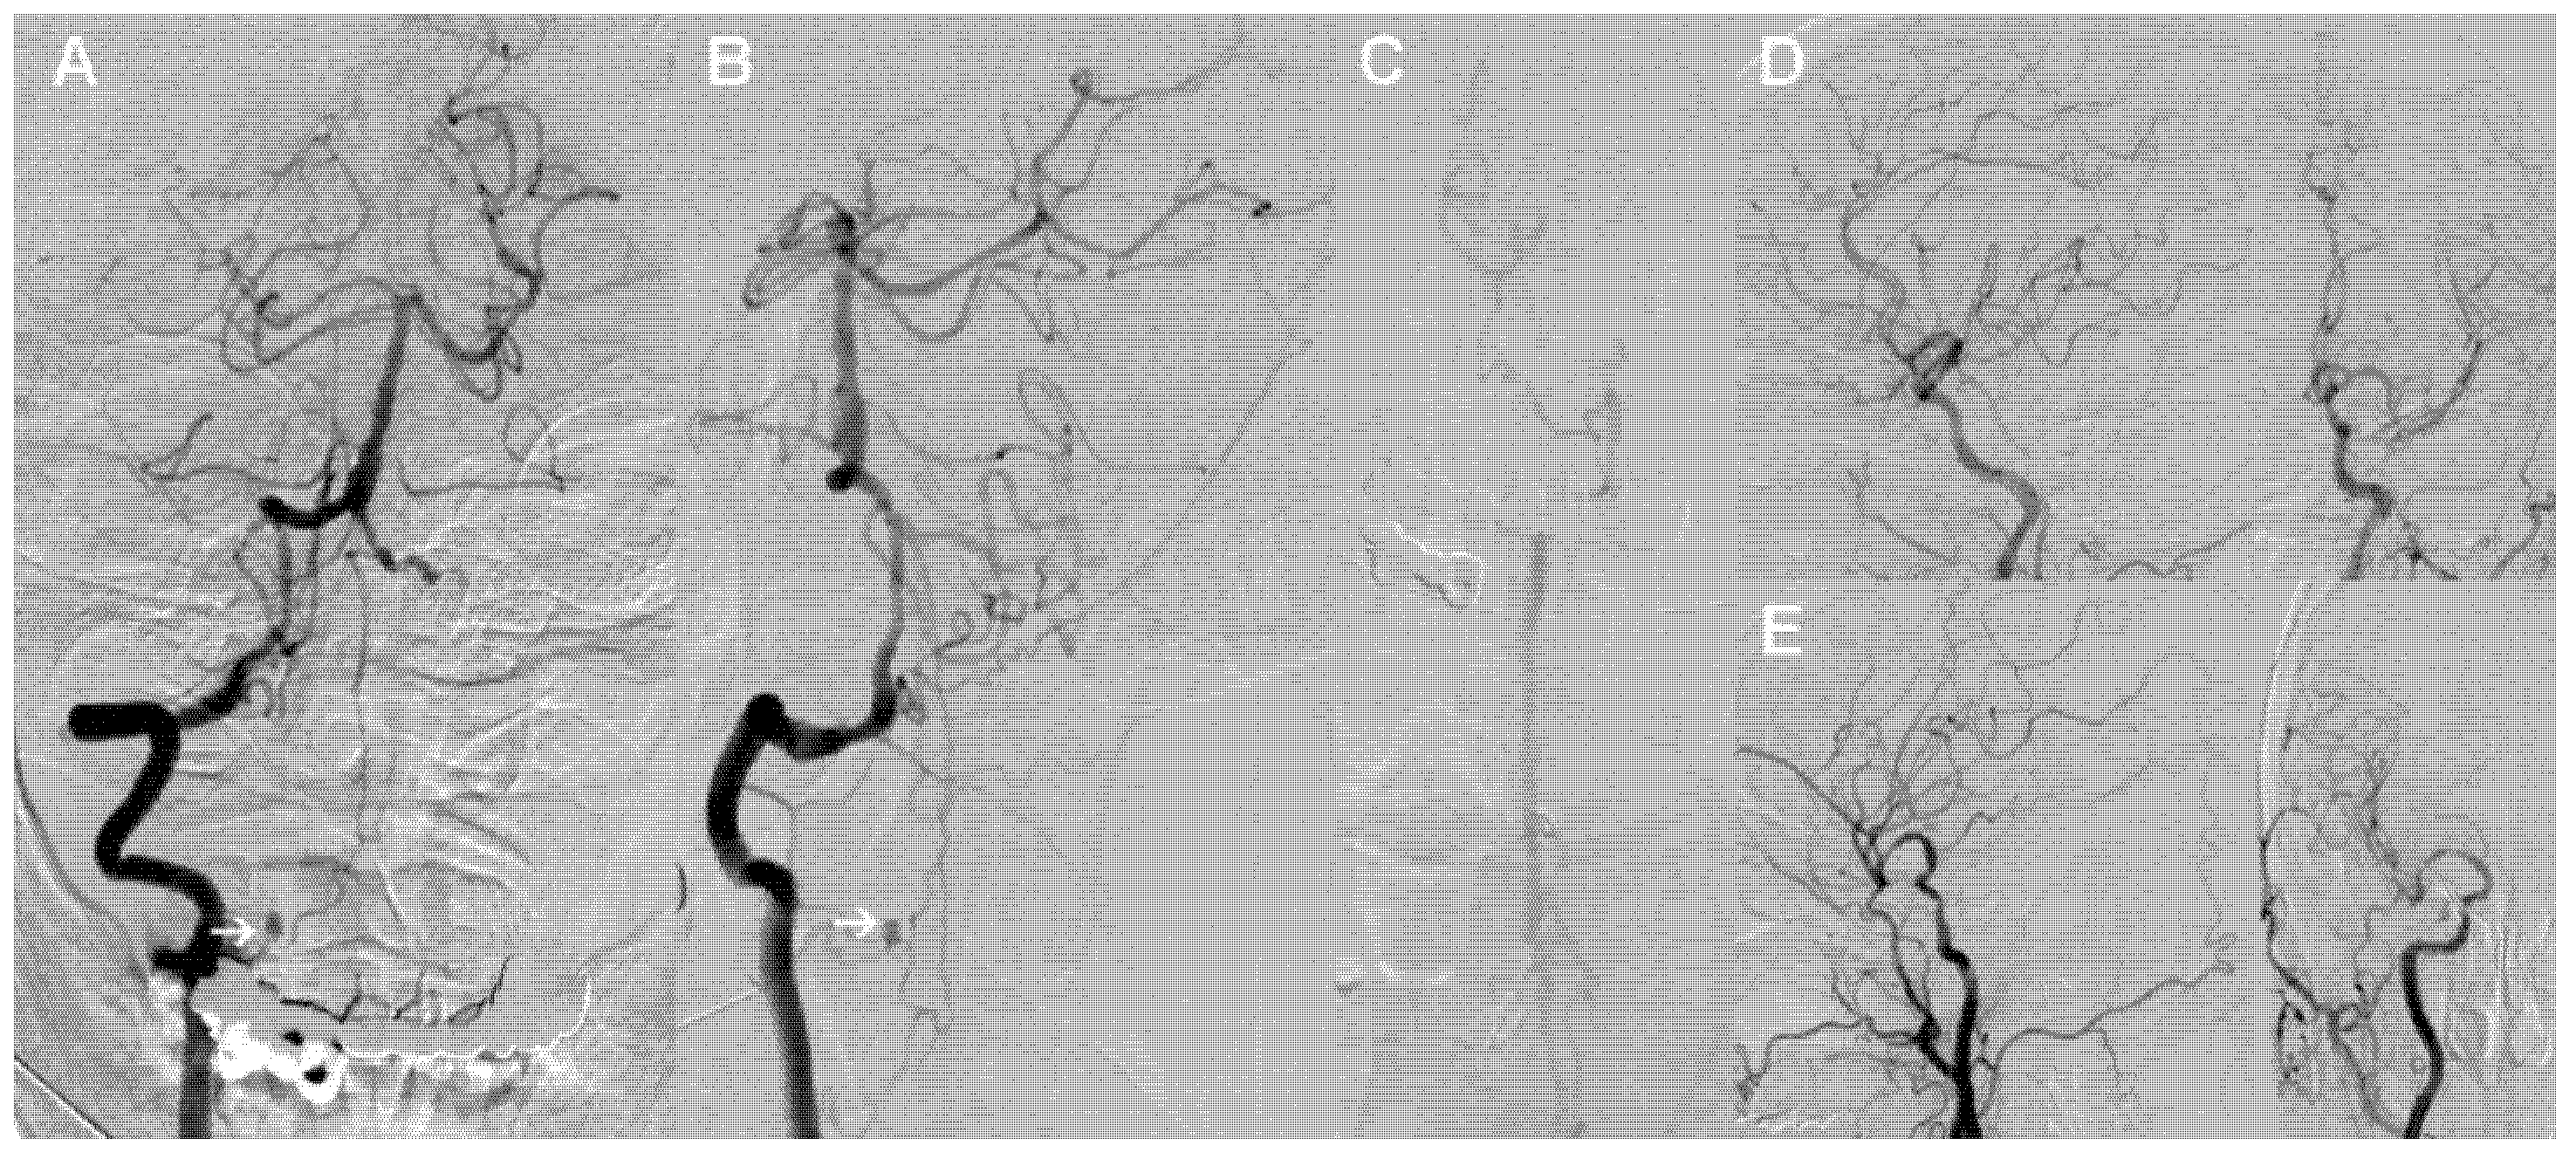

2. Case Presentation